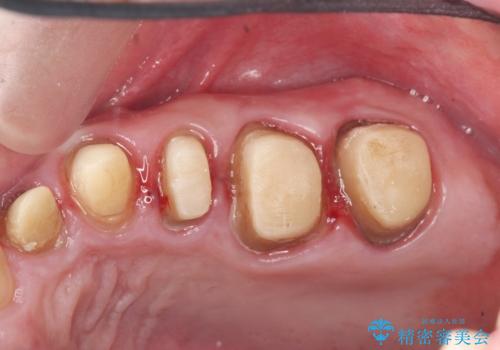

虫歯の徹底的な除去やセラミック補綴、精密根管治療、歯周外科を行うことで、治療後に歯磨きがしやすく、かみやすい機能的な仕上がりへと導きます。

- 63.8万円(ジルコニアクラウン×4・仮歯×4・歯周外科) (上顎左側臼歯4本分の費用)費用は治療当時の料金となります

歯周外科手術をおこなったことでフェルールも獲得でき、破折リスクをより抑えることにも成功しています。